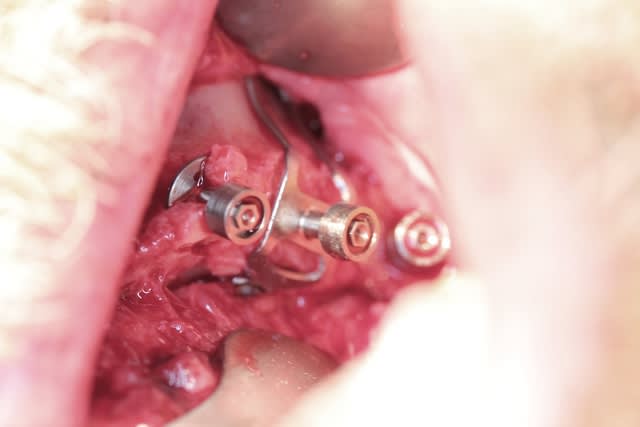

Bref 2 ptérygo, 2 plaques en molaires, deux disk en canine 1 simple et un double, un cylindre ds le trou naso palatin, 2 triple disk en 11 12 et 21 22 et enfin un monodisk en 24...ça a été galère mais c est fait

Opéré mardi matin

Photos un peu flou car implanto chaude et j ai pris juste l appareil deux fois pour tirer le portrait des deux plaques